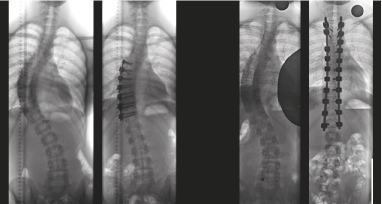

Indien de scoliose ondanks alle maatregelen blijft toenemen of  meer dan 40° à 50° bedraagt, zal eventueel een operatie worden overwogen. De operatie bestaat uit het rechtzetten van de rug met behulp van titanium staven en schroeven, waarmee een aantal wervels worden vastgezet. De rug wordt hierdoor wat stijver, maar dit geeft vaak weinig aanleiding tot problemen. De scoliose-operatie blijft echter een laatste oplossing, wanneer brace en oefentherapie niet voldoende blijken te zijn.